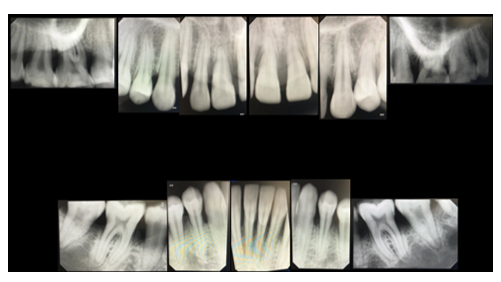

Figure 4 Baseline periapical radiographs (2023)